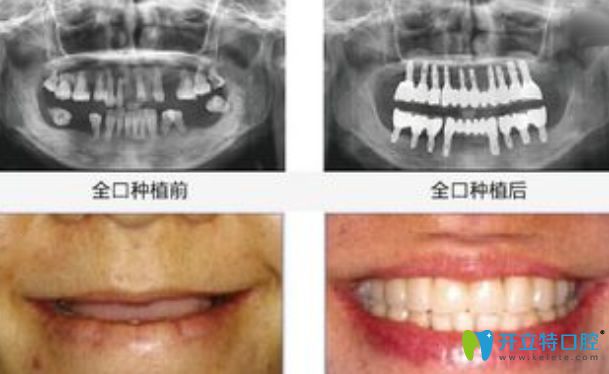

全口種植牙前后對比圖

對于有些年輕人會覺得3-6個月時間太長,影響個人形象和工作,那就來看比種植牙更好的方法:

比種植牙更好的方法就是即刻種植牙,這種方法不用等3-6個月,可以實現(xiàn)當天拔牙、種牙、戴牙冠,整個手術時間為2小時左右,而且當天就可以吃東西。